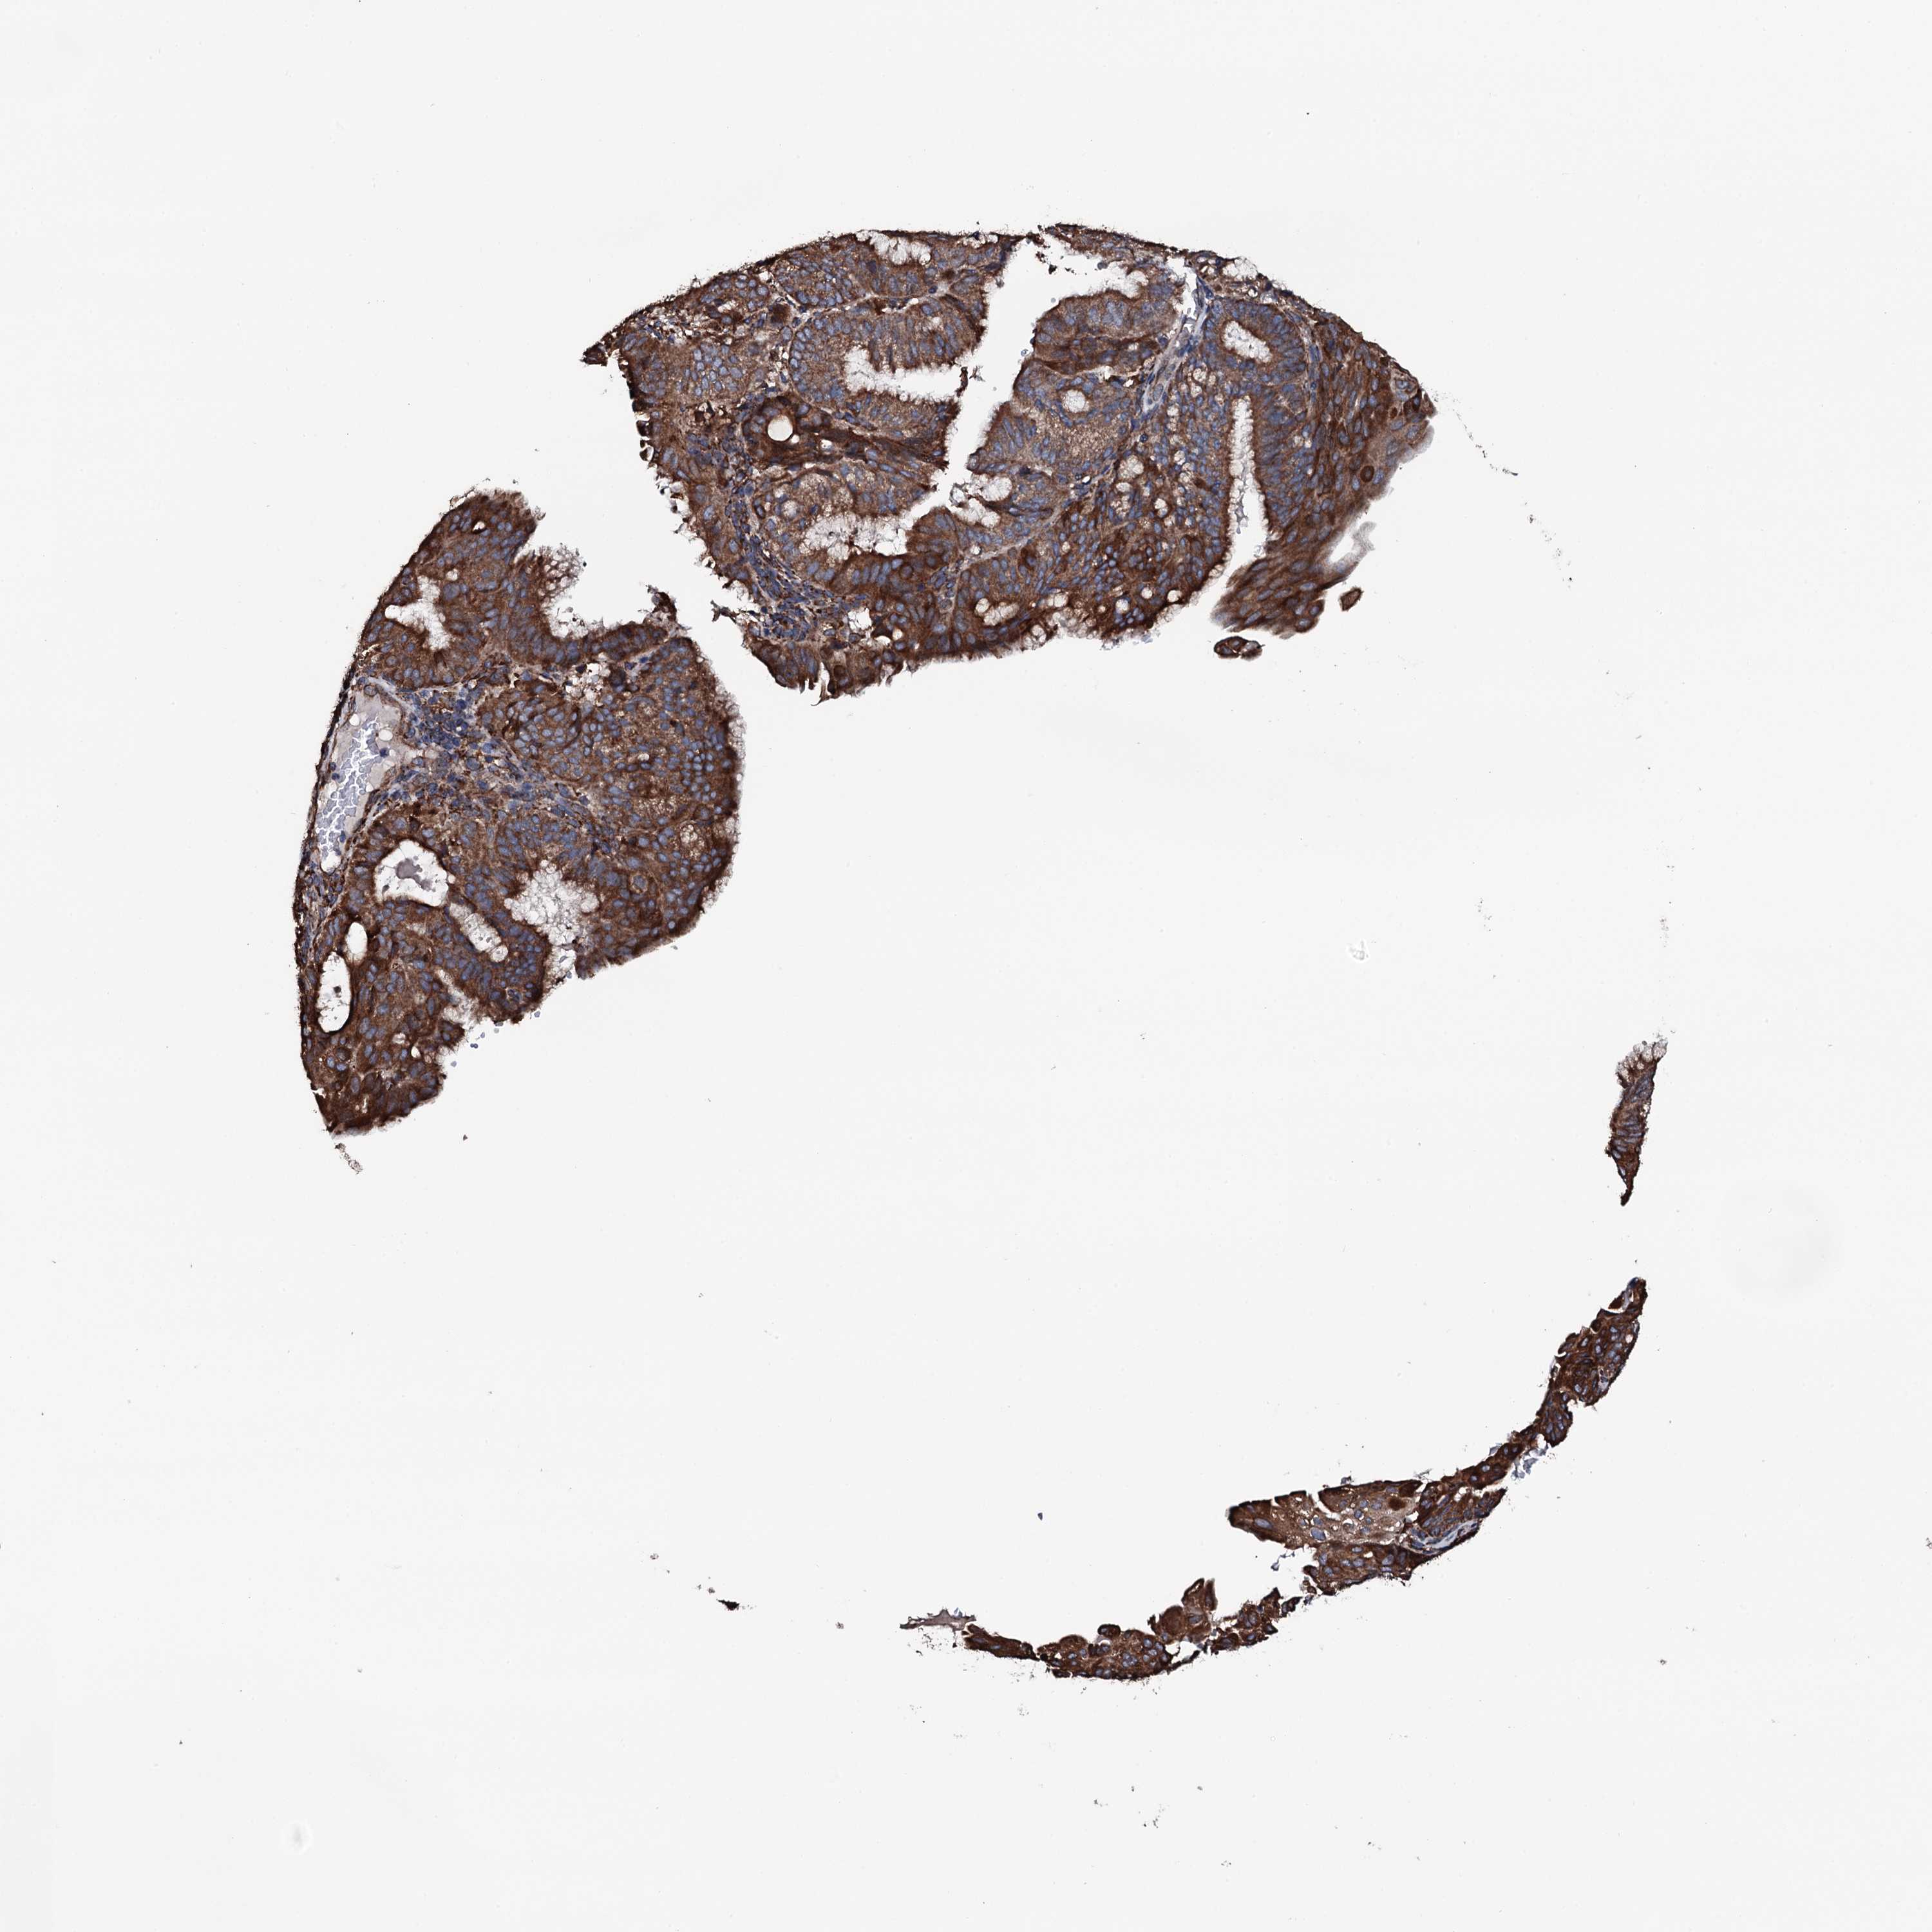

ENDOMETRIAL CANCER - Protein expressioni

A mouse-over function shows sample information and annotation data. Click on an image to view it in a full screen mode. Samples can be filtered based on level of antibody staining by selecting one or several of the following categories: high, medium, low and not detected. The assay and annotation is described here.

Note that samples used for immunohistochemistry by the Human Protein Atlas do not correspond to samples in the TCGA dataset.

Antibody stainingi

Antibody staining in the annotated cell types in the current human tissue is reported as not detected, low, medium, or high, based on conventional immunohistochemistry profiling in selected tissues. This score is based on the combination of the staining intensity and fraction of stained cells.

Each image is clickable and will lead to virtual microscopy that enables deeper exploration of all samples and also displays staining intensity scores, fraction scores and subcellular localization as well as patient and tissue information for each sample.

Antibody HPA040727

Staining

High

Medium

Low

Not detected

Intensity

Strong

Moderate

Weak

Negative

Quantity

>75%

75%-25%

<25%

None

Location

Nuclear

Cytoplasmic/membranous

Cytoplasmic/membranous,nuclear

Adenocarcinoma, NOS